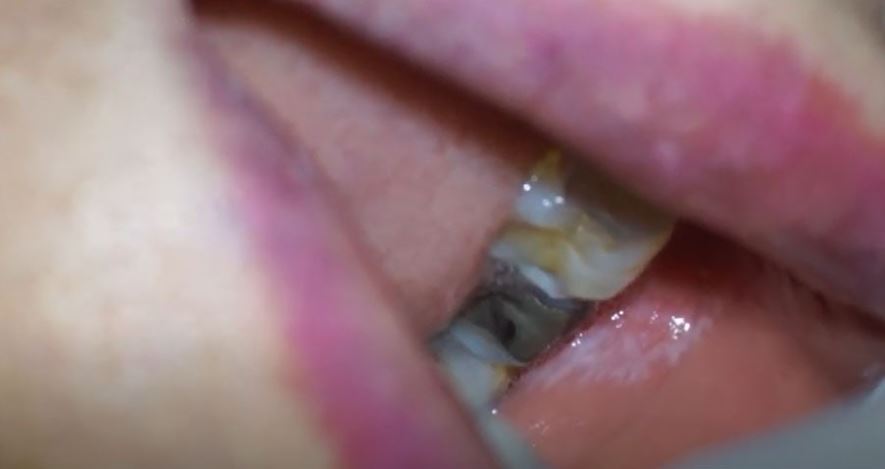

특히 구강 점막에 생긴 편평태선을 구강편평태선이라고 하며,

주로 볼 안쪽, 입천장(구개), 입술 안쪽 등에서 발생합니다.

아래 사진은 입술 안쪽, 즉 구순 내측에

발생한 구강편평태선의 모습입니다.

그물처럼 보이는 발진이 전형적인 형태입니다.

가장 흔하게는 볼 안쪽에 발생하며, 하얀색 또는 회색빛을

띠는 전형적인 망상(레이스) 모양이 관찰됩니다.